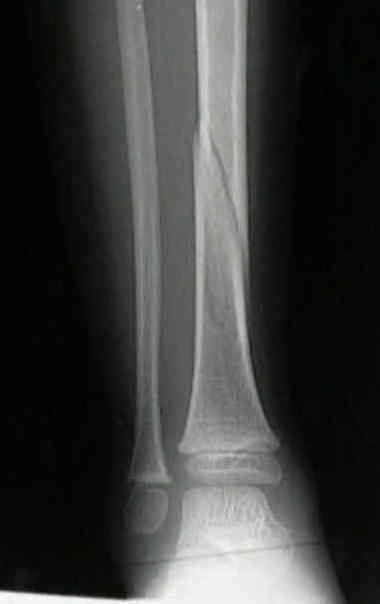

spiral/ oblique fracture